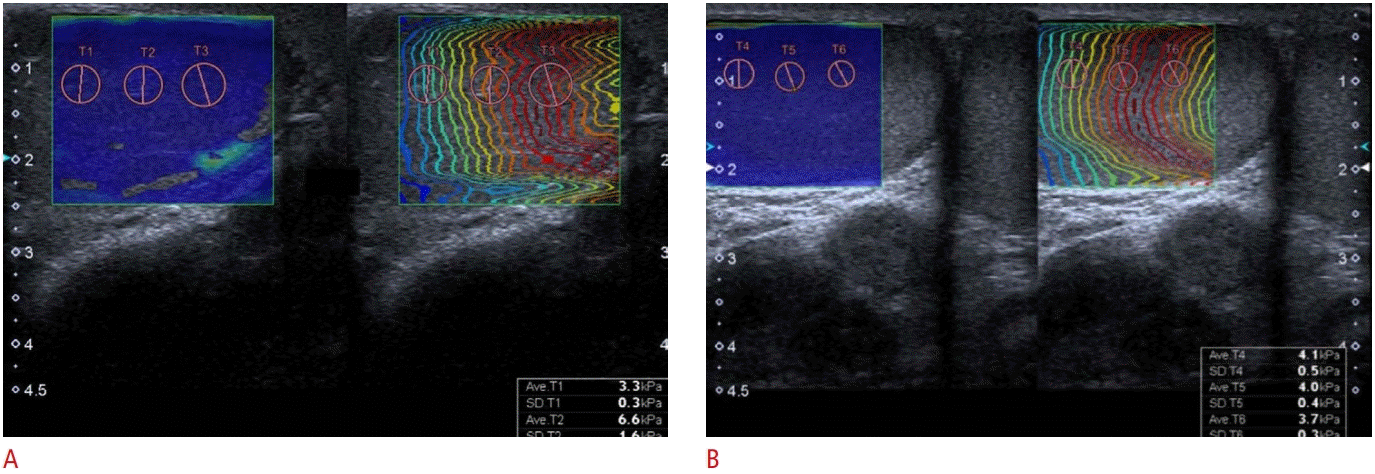

An observer with more than 8 years of experience with conventional US and elastography experience (O.T.) performed all examinations. The patients were asked to lie in the supine position before the measurements. All grayscale and SWE examinations were performed using an Aplio 500 Platinum (Canon, Tokyo, Japan) US unit. The measurements were conducted using a linear array high-frequency transducer (11-14 MHz). The testicular volumes were calculated from 2-dimensional images using the prolate ellipsoid method based on the formula: volume=length×width×height×0.523. During this phase of the measurements, patients were excluded from the study if the observer identified any abnormalities in the testicular parenchyma on grayscale US or did not confirm the presence of varicocele by a US assessment. After completing the conventional US evaluation, the observer initiated the SWE examination. While performing the SWE examination, the observer kept the transducer as stable as possible to avoid artifacts. Images that were taken longitudinally were chosen for the measurements. The observer placed three regions of interest with a diameter of 3 or 4 mm onto the chromatic box using propagation maps, and performed five consecutive measurements. The average of these measurements was calculated. The stiffness values were recorded in units of kilopascals (kPa). Fig. 2 shows the SWE evaluation of a testis with varicocele and a contralateral normal testis. The left testes of patients with varicocele were further categorized into groups A and B according to total sperm count, with group A constituting patients with normal spermiograms, while group B constituted patients with oligospermia (sperm count <15 million/mL). The mean SWE and volume values of the left testes of patients were compared with those of the contralateral testes and the testes of the healthy controls.

Fig. 2.

A 25-year-old normospermic man with left-sided varicocele.

The average stiffness (4.86 kPa) value of the left testis (A) derived from three regions of interest was higher than that of the contralateral (B) testis (3.93 kPa).